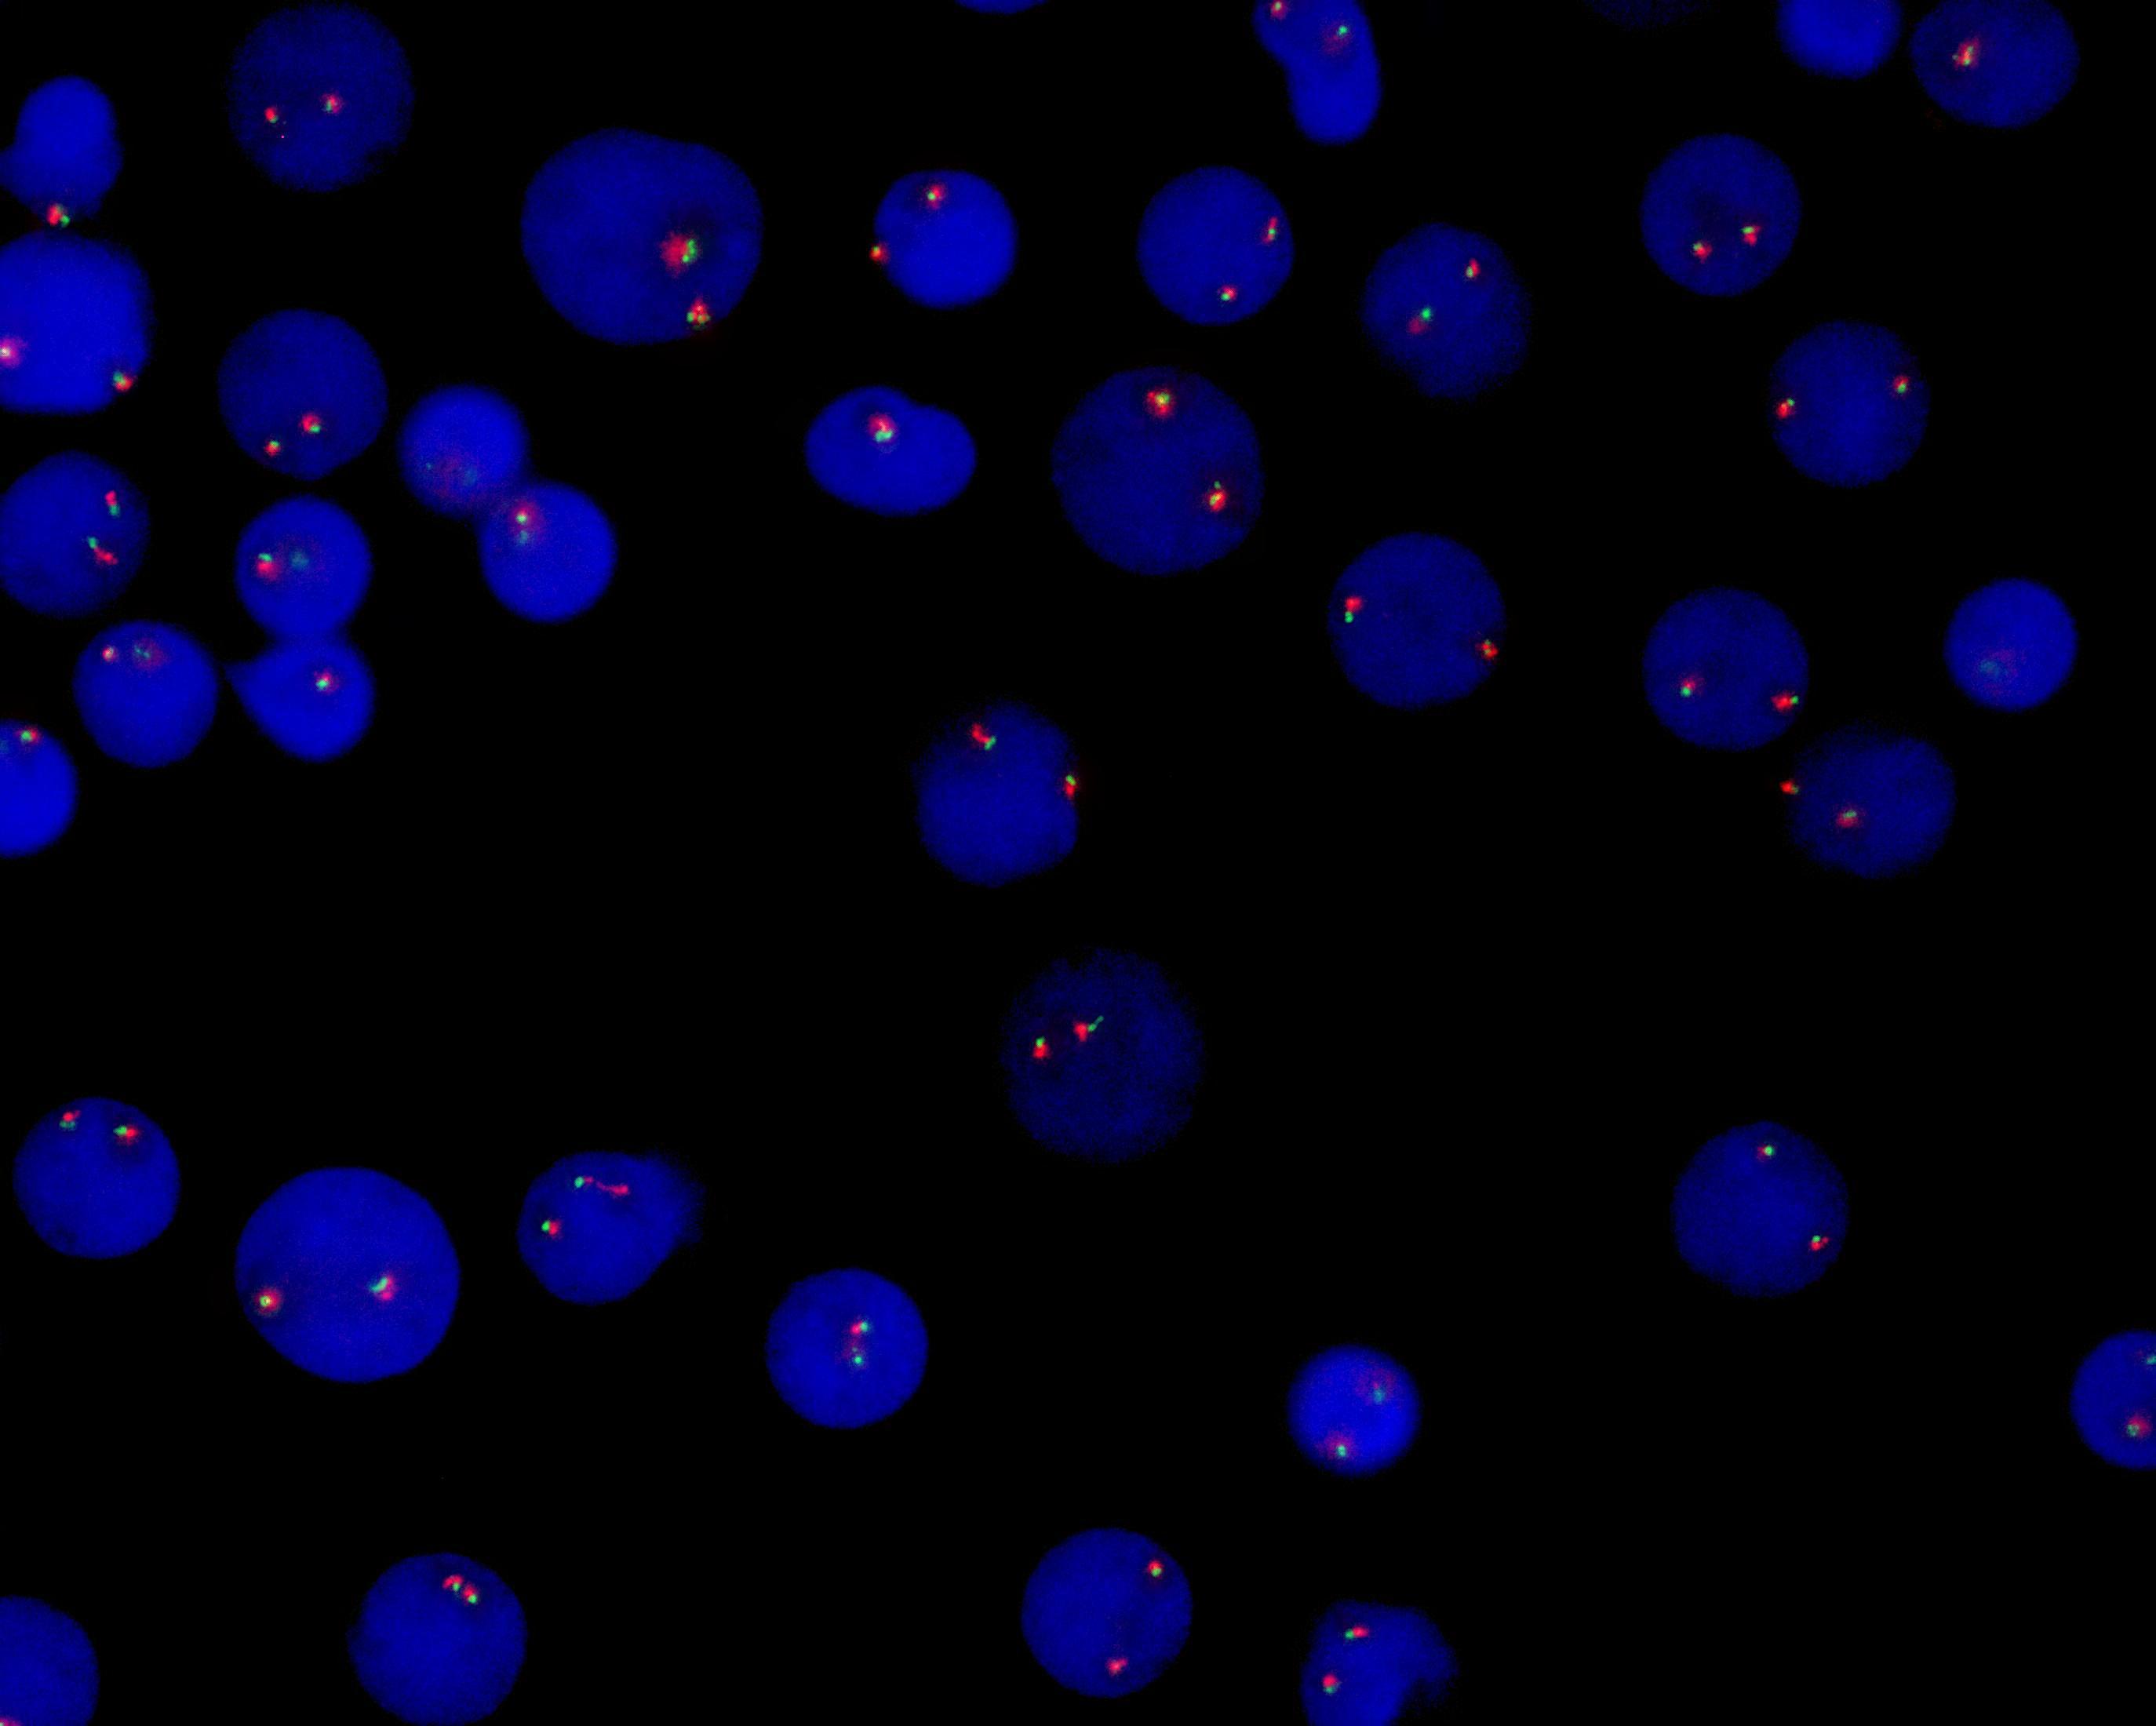

KMT2A (MLL) gene break apart probe reagent

MLL dual color probe

KMT2A (MLL) gene 5’ end labeled as green, with a length of 440 kb; KMT2A (MLL) gene 3’ end labeled as orange, with a length of 290 kb.